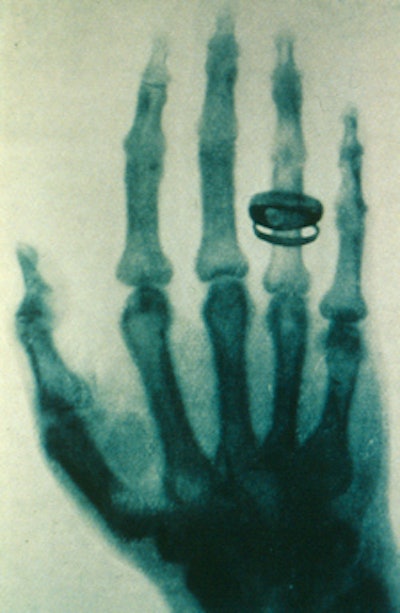

One of Röntgen's early images.

One night, to explain his experiment to his wife, he made an x-ray image of her hand. The bones and the ring appeared, but the flesh was not seen. His wife was frightened, but Röntgen was convinced that he understood the presence of the invisible x-rays and their ability to make images of dense objects and living human bones.